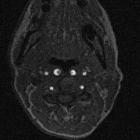

Kissing

carotids: a lovely term for an anatomic variant with great clinical significance. This axial MDCT image shows the level where the two ICA (arrows) are situated in the retropharyngeal space and in close proximity (4mm). The right ICA is more hyperdense than the left due to artefacts.